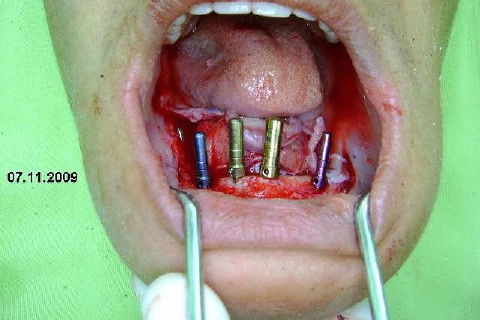

Apesar da boa adaptação e estética satisfatória, a principal queixa da paciente era a instabilidade da prótese inferior, como sempre ocorre nestes casos...atrofia do rebordo alveolar e perda da função mastigatória.